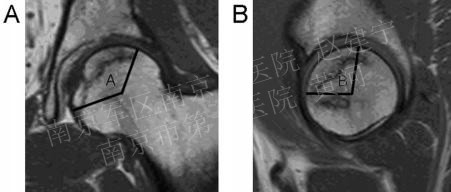

预后的判断:病损区体积的大小是判断ONFH预后的重要参数,基于髋关节MR之上的改良Kerboul测量法在临床上应用的较为广泛,A与B之和(联合坏死角)如大于200°,通常预示着股骨头的塌陷及病情的进展。